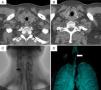

Patient no. 3A 44-year-old man had been diagnosed with GPA at the age of 39 years. Two months after the diagnosis, he presented with laryngeal stridor, dyspnea, foreign body sensation in his larynx and dysphonia. Fiberoptic laryngoscopy revealed SGS of 20% with systemic activity (BVAS score of 23). He was treated with 3 doses of 1g/day of methylprednisolone and intravenous cyclophosphamide; the systemic manifestations remitted, but his dysphonia, stridor and dyspnea progressed. One month later, CT revealed concentric circumferential thickening that partially obstructed the tracheal lumen (Fig. 2 A and B). Bronchoscopy showed SGS of 70%, with erythematous laryngeal structures. He received 3 doses of 1g/day of methylprednisolone and underwent tracheal dilatation. Subsequently, the clinical course was satisfactory, with remission of the stridor and improvement in the symptoms. However, 7 days later, his symptoms recurred, with 100% restenosis (Fig. 2C and D), which required emergency tracheostomy.

Computed tomography of larynx and trachea in patient no. 3. (A and B) Axial images showing the subglottic stenosis with concentric circumferential thickening of the mucosa (*) partially obstructing the tracheal lumen. (C) Subglottic stenosis (arrow). (D) Volumetric reconstruction of subglottic stenosis (arrow).